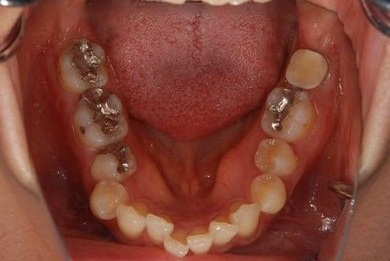

| 性別/年齢 | 女性 / 37歳 | ||||||||||||||||||||||||||||||||

| 主訴 | 左奥歯を抜歯した際、インプラントをするにはほおの一部を移植すると言われたが、他の先生の意見を伺いたい。 | ||||||||||||||||||||||||||||||||

| 治療内容 | インプラント1本、メタルボンドセラミッククラウン1本 | ||||||||||||||||||||||||||||||||

| 総治療費 | 252,000円 | ||||||||||||||||||||||||||||||||

| 治療期間 | 6ヶ月 |